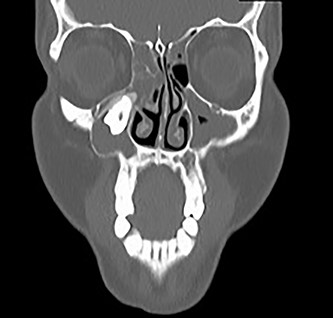

A 29-year-old female patient was referred from the Maxillofacial surgeons to ENT outpatients, for assessment of a loose upper right molar and right-sided retro-orbital pain, ongoing for 4 months. She had no past medical or surgical history and was a lifelong non-smoker with no significant family history. Imaging with a orthopantomogram (Fig. 1) depicted an ectopic tooth in the right maxillary sinus. CT imaging further characterized a thin-walled cystic mass in the right maxillary sinus (Figs 2 and 3), and opacification of the maxillary and ethmoidal air cells is also visualized alongside the afore mentioned ectopic tooth.

Coronal CT image of the right ectopic tooth at the antrum of the right maxillary sinus.

Sagittal CT image of the right ectopic tooth at the antrum of the right maxillary sinus.

OKCs of the maxilla are atypical, and they are more often found in the canine region. The findings on CT imaging located the cyst base at the second upper molar, and this would be more representative of a radicular cyst. The ectopic eruption of teeth in regions other than the oral cavity is rare [6], though they have been reported. However, to find a tooth at the osteomeatal complex is extremely atypical, there is postulation that with the development of an OKC, it encroaches on the space of the sinus and displaces its borders, displacing teeth buds and resulting in an eruption of an ectopic tooth [7].